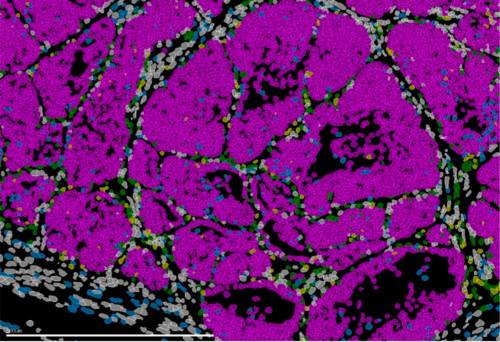

Este es el atlas del envejecimiento del músculo esquelético humano

Un estudio, publicado en Nature, proporciona una base para el desarrollo de estrategias preventivas y terapéuticas en los ancianos con el análisis de la expresión génica y epigenética de las células de este tipo de músculo a diferentes edades.